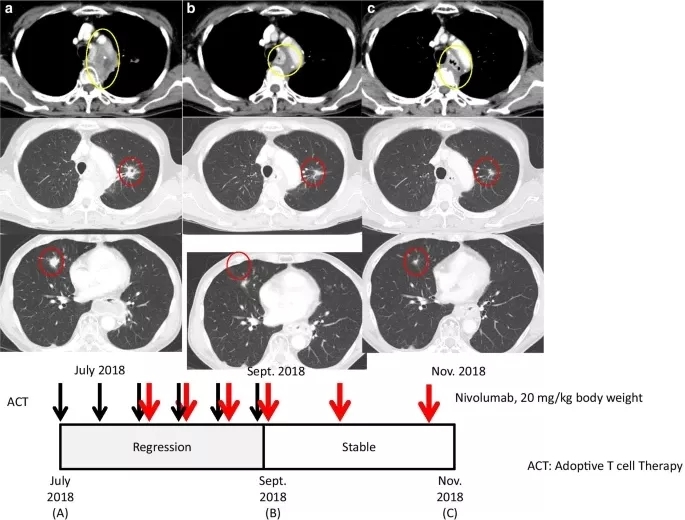

2018年7月,患者报名参加了作者所在医院的一项临床试验(临床试验编号UMIN000028756)(图1a)。在开始临床试验前,作者团队利用患者的肿瘤标本评估了PD-L1表达水平,发现肿瘤组织中PD-L1表达水平小于1%。肿瘤微卫星不稳定(MSI;数据未显示)。患者以2周为间隔接受2次ACT治疗,随后以0.3 mg/kg体重的剂量接受纳武利尤单抗治疗,以2周为间隔接受4次ACT治疗,作为诱导治疗的一部分。

2018年9月19日(纳武利尤单抗启动后9周)的随访CT扫描显示部分缓解,肺转移灶和纵隔病变体积减少48%(图1b)。患者继续接受剂量为40 mg/kg体重的纳武利尤单抗作为维持治疗(时间间隔为3周)。2018年随着患者的临床进程,X线拍片显示有轻微改善(图1c),由于患者临床状态良好且存活,因此继续应用纳武利尤单抗维持治疗。患者有轻微但无症状的甲状腺功能减退,需要补充甲状腺激素,然而患者并没有显示其他临床显著的治疗相关毒性。

图1. 病例1的临床病程

轴位CT图像对应于治疗和疾病状态的时间线。黄圈表示纵隔病变,红圈表示肺转移病灶。a.(上)使用纳武利尤单抗治疗前的状态。b. 过继细胞治疗(ACT)和免疫检查点抑制剂(ICI)联合治疗后纵隔和肺转移灶的消退。在ICI维持治疗期间,反应持续(c)。黑色和红色箭头分别表示ACT和纳武利尤单抗给药(下)。